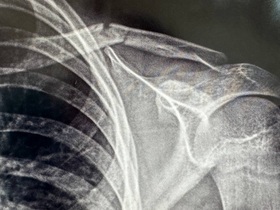

Остеосинтез плеча при вывихе ДО-ПОСЛЕ: